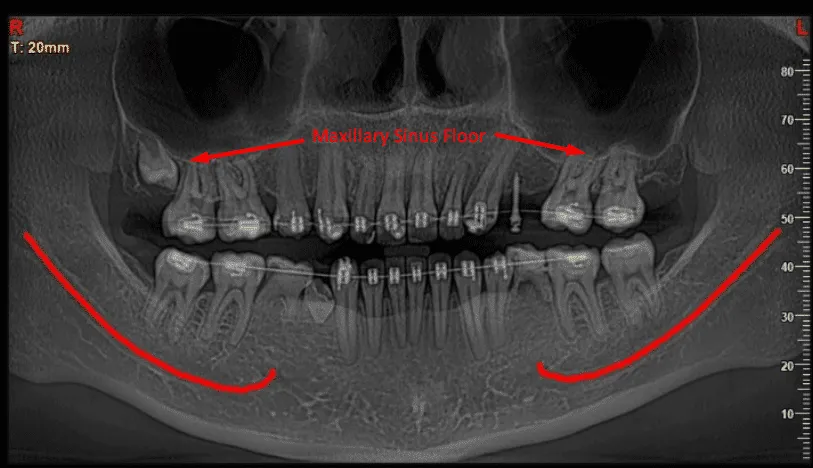

The upper jawbone, specifically the area around the molars and premolars, often presents a challenge when it comes to dental implants. This is primarily due to the proximity of the maxillary sinuses, which can limit the amount of bone available for successful implant placement.

Many individuals who have lost teeth in this area experience bone resorption, where the jawbone diminishes in density and volume over time. This can result from tooth loss, periodontal disease, or natural aging processes. For patients considering dental implants, insufficient bone mass can compromise the stability and longevity of the implant, making it crucial to address this issue before proceeding.

This not only enhances the chances of successful integration of the implants with the jawbone but also improves overall oral health. The need for such a procedure is often identified through comprehensive dental examinations, where imaging techniques like X-rays or 3D scans reveal the extent of bone loss and the condition of the sinus cavities.